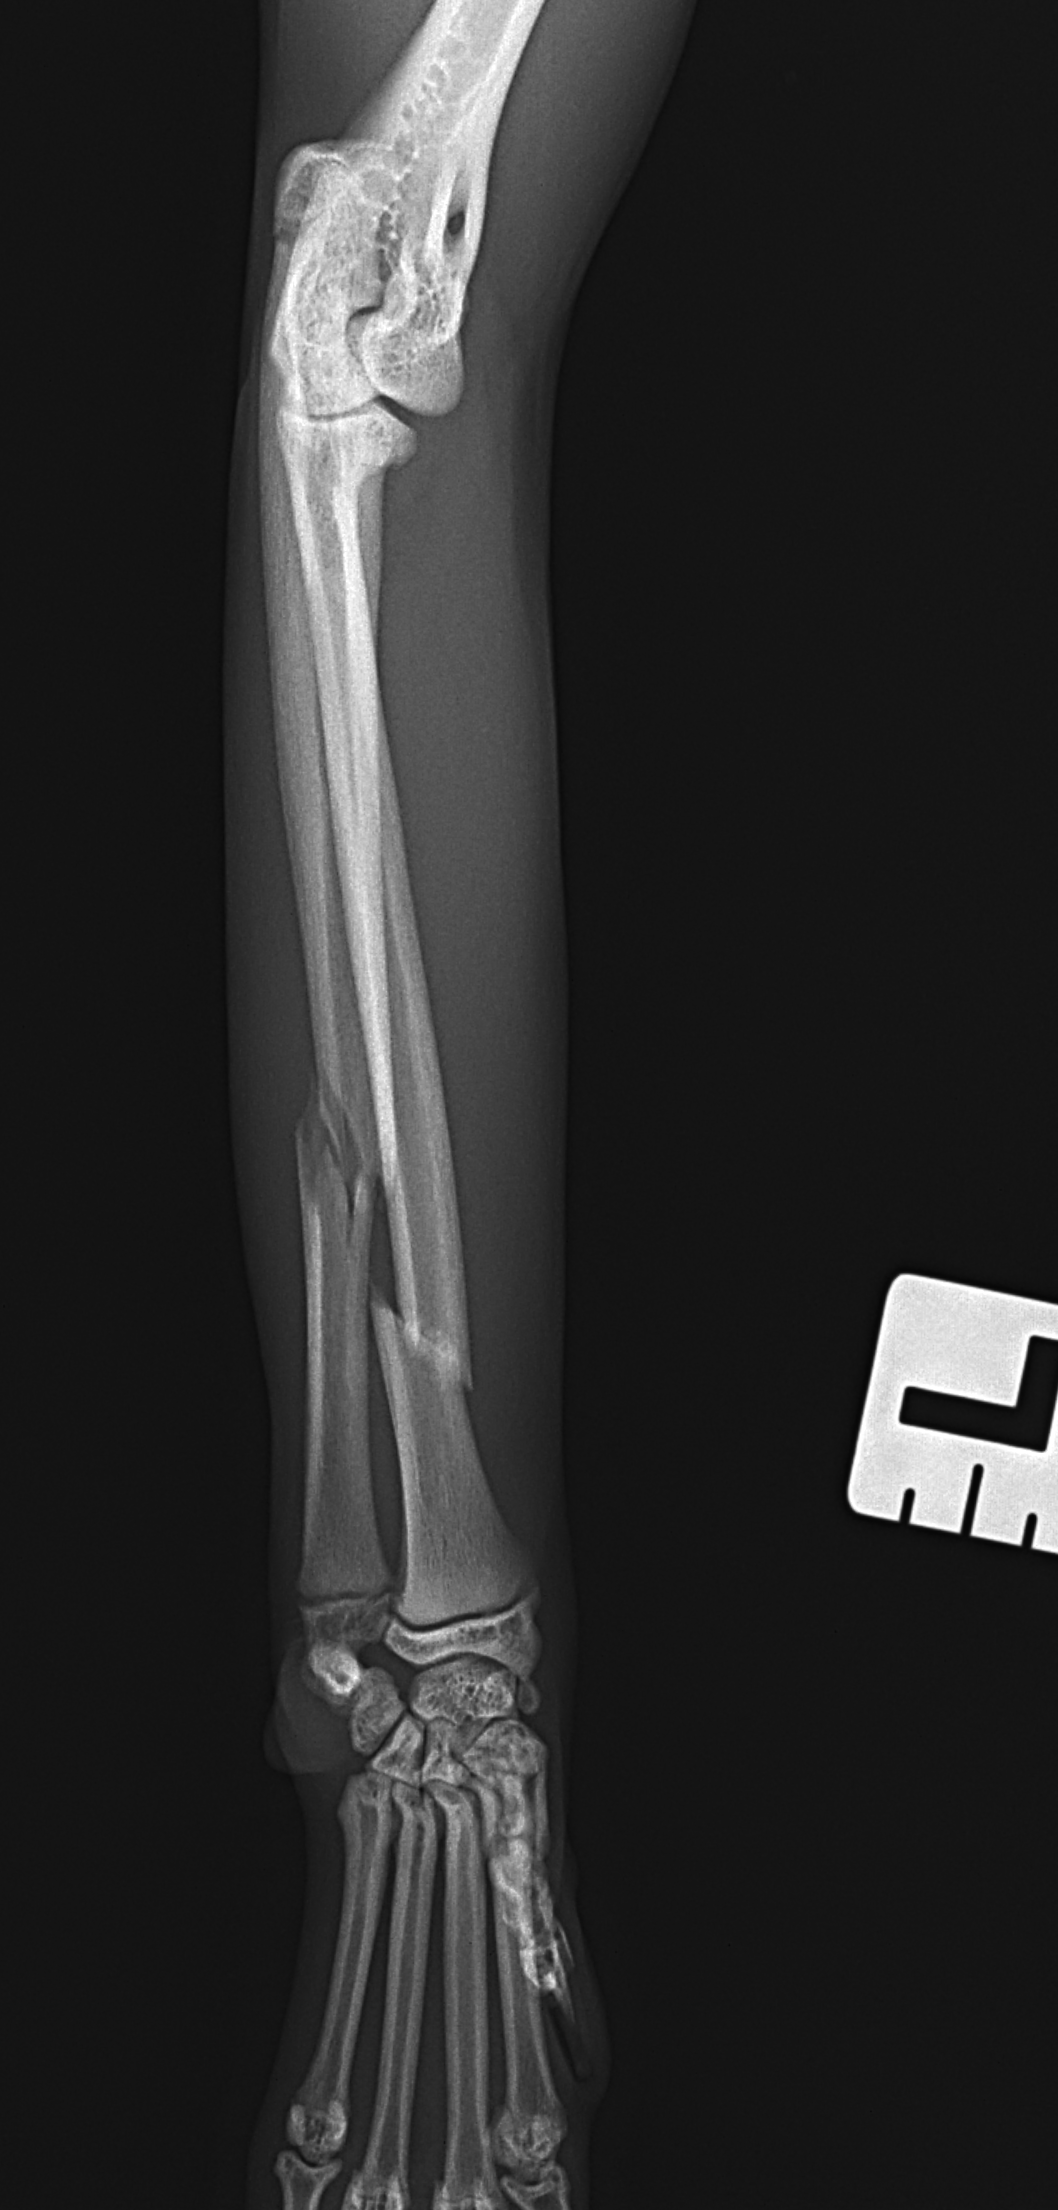

猫さんがご自宅の2Fから落下したとのことで、かかりつけ医を受診されました。右の橈骨尺骨骨折が確認されました。2.4 Titnium Locking Plate(Distal 3holeストレート)、尺骨1.6mm Titanium Wireで固定術を行いました。猫は高いところで遊ぶのが好きな動物なので、遊び場に危険な場所がないか?生活環境を見直す必要があります。